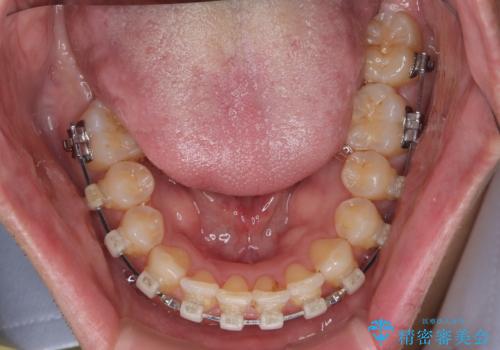

- クリアブラケット

- 1年1ヶ月

- 10-30回

ワイヤー矯正でもマウスピース矯正でも可能でしたが、短期間で、自身の手を煩わせることなく治療を行いたいとのことで、ワイヤー装置にて矯正治療を行うこととしました。

上顎前歯の舌側転位が顕著であったため、治療期間が長くなると思われましたが、僅か1年で無事に終えることができました。